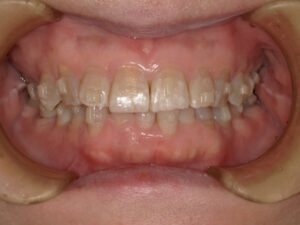

笑った時に、歯ぐきが見えるのをガミースマイルと言います。

ガミースマイル(Gummy Smile)とは、笑ったときに上唇が上がって、歯ぐき(歯肉)がよく見えてしまう状態を指します。審美的な問題として気にされる方が、ことのほか多いです。原因も様々で、それぞれ治療法が異なります。歯科的な治療法と歯科以外の治療法を説明していきます。ただし原因にかかわらず、治療による改善は難しいことが多いです。